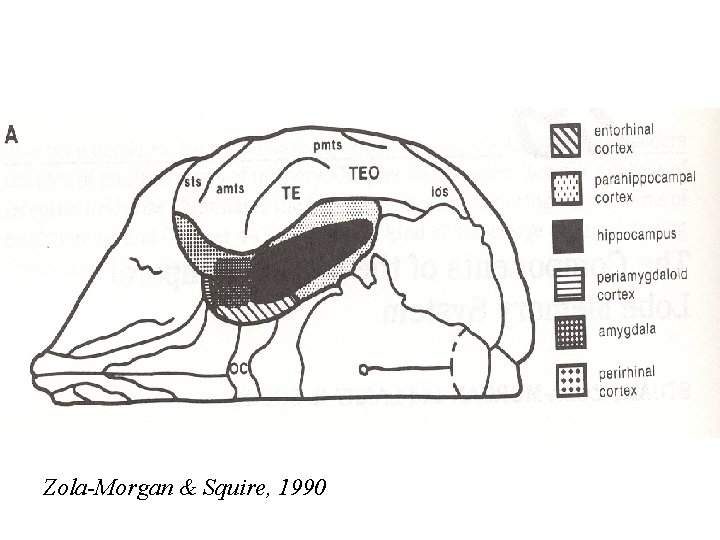

Zola-Morgan & Squire, 1990

Zola-Morgan & Squire, 1990